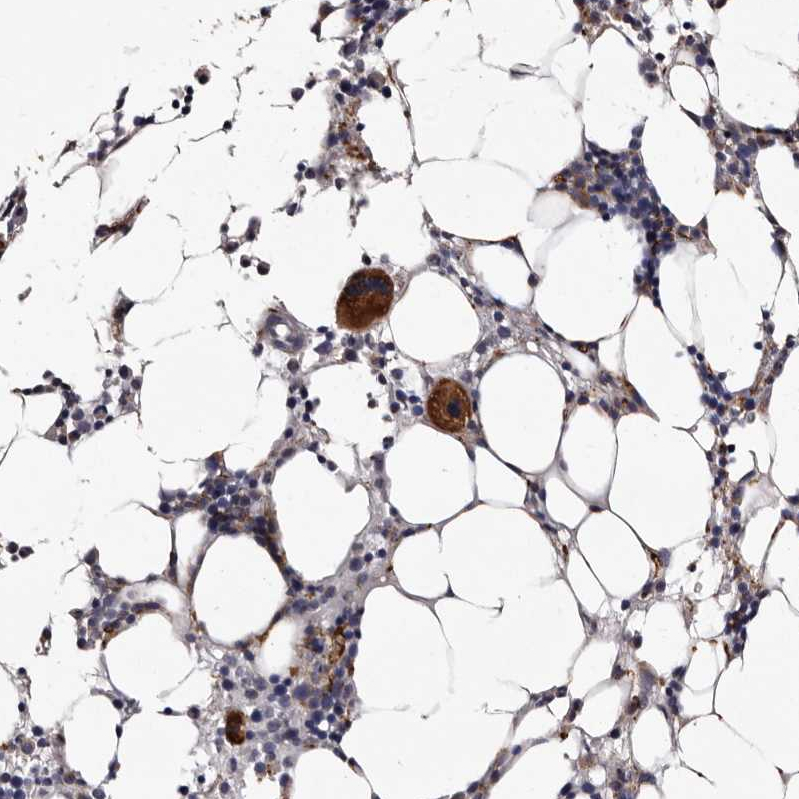

Immunohistochemical staining of human malignant melanoma shows strong cytoplasmic positivity in tumor cells.